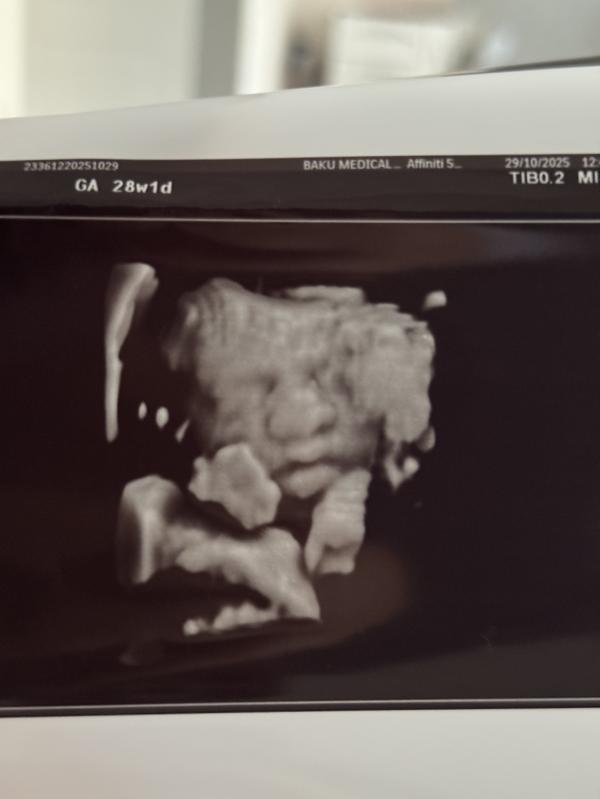

Всем привет 🙏🏻была я на узи сегодня все нормально шукур 🙏🏻вот только плацента не поднялась 😔но врач сказал не страшно все равно кс будет но надо беречь чтоб не кровило 🙏🏻но слава Аллаху все остальное хорошо и малышка тоже активная растёт 1.334 гр уже Машаллах 🙏🏻только хочу саг саламат родить во время 🙏🏻